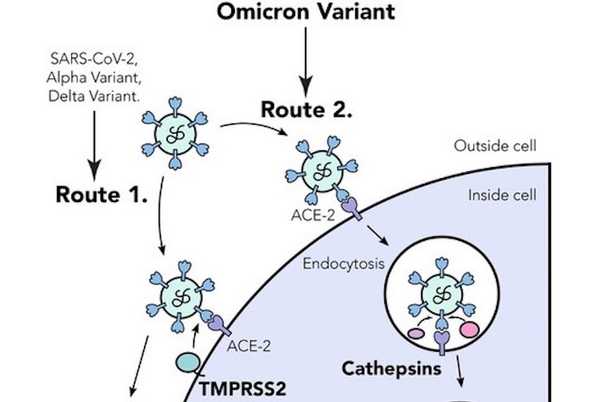

Για να κατανοήσει πόσο αποτελεσματική είναι η omicron στην είσοδο στα κύτταρα, η ομάδα χρησιμοποίησε τους συνθετικούς ιούς για να μολύνει κύτταρα σε οργανοειδή πνεύμονα.

Το Πανεπιστήμιο του Κέιμπριτζ εξήγησε σε μια ανακοίνωση ότι παρά το γεγονός ότι είχε τρεις μεταλλάξεις που προβλεπόταν ότι ευνοούσαν τη διάσπαση της ακίδας, η πρωτεΐνη ακίδας omicron βρέθηκε να είναι λιγότερο αποτελεσματική από την ακίδα δέλτα στη διάσπαση του υποδοχέα πρωτεΐνης ACE2 – που βρίσκεται στην επιφάνεια των κυττάρων στον πνεύμονα – και εισέρχεται στα πνευμονικά κύτταρα.

Μόλις η όμικρον εισήλθε στα πνευμονικά κύτταρα μετά τη διάσπαση του υποδοχέα ACE2, ήταν επίσης λιγότερο ικανή από τη δέλτα να προκαλέσει σύντηξη μεταξύ των κυττάρων – κάτι που παρατηρείται συχνά στους αναπνευστικούς ιστούς που λαμβάνονται μετά από σοβαρή ασθένεια.